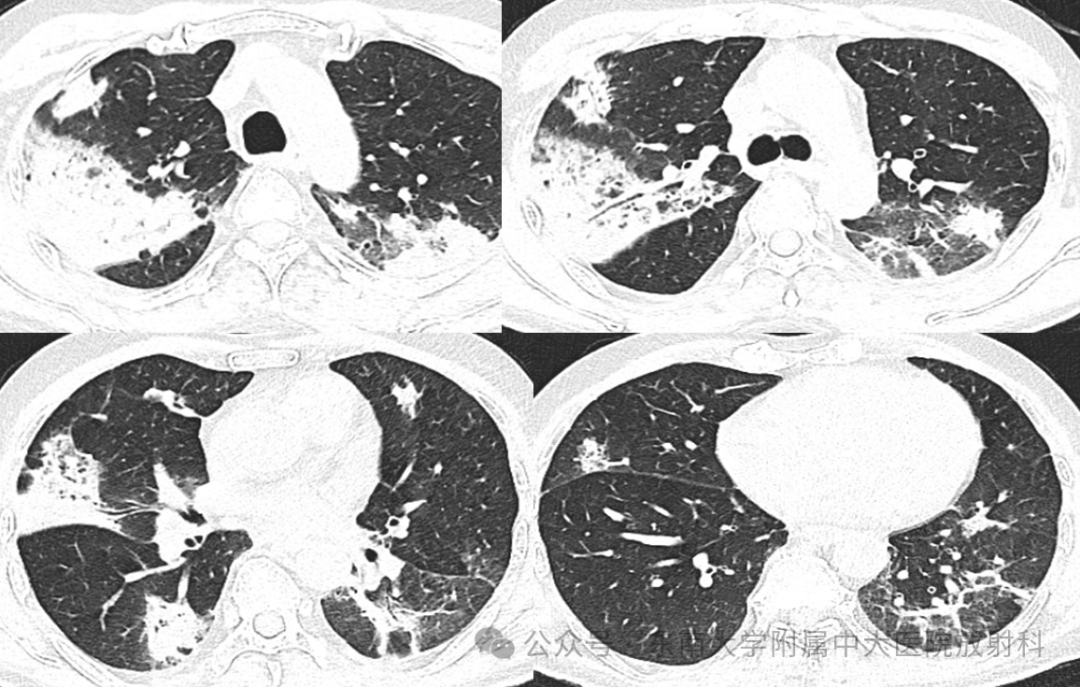

从影像学看机化性肺炎的特征

• 现病史:患者2年前(2023-10)确诊食管癌,予以依托泊、顺铂、斯鲁利单抗治疗,病情稳定后患者斯鲁利单抗免疫维持治疗。2024-9-21外院复查CT提示两下肺纵隔旁炎症,暂停免疫治疗。2024-12-02外院CT复查CT示两肺部分病灶较前吸收好转,部分较前明显或新见;2024-12-04号来我院住院治疗,支气管镜(左下叶前基底段活检)病理提示炎症伴机化,予以甲泼尼龙治疗症状好转后予以出院,2025-01-07复查CT提示两肺病灶明显吸收降;2025-04-12、05-03、05-24共3次使用斯鲁利单抗免疫治疗,患者06-10起出现咳嗽咳痰伴胸痛,06-17外院CT示左肺下叶炎症,后至我院住院,予哌拉西林钠他唑巴坦钠感染治疗;07-02复查胸部CT,病灶吸收不明显,建议患者行气管镜治疗,患者考虑后表示暂不行气管镜,要求出院(出院带药奈诺沙、溴己新)。出院后仍有反复咳嗽,08-12再次我院就诊

2025-08-12 CT

图片